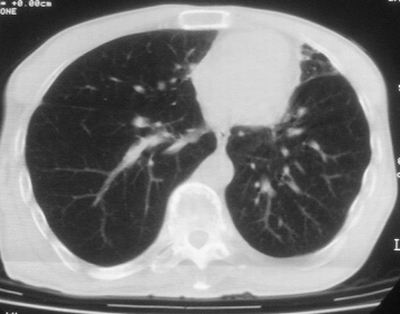

标题: CT11864:男,47岁,反复咳嗽、咯痰、咯血3年,请分析. [打印本页]

患者,男,47岁,反复咳嗽、咯痰、咯血3年,再发5天。痰培养未找到真菌、抗酸杆菌、癌细胞。

左上肺肺结核可能。左下肺合并感染

左肺上叶体积明显缩小,其内见多发透光区,纵隔向左侧移位,左肺下叶多发班片状病灶,边界模糊,1左肺上叶先天肺发育不全,2左肺下叶肺炎,

左肺上叶结核伴肺纤维化,纵隔移位,左肺下叶感染性病变,建议抗炎抗结核后复查,双肺气肿.

考虑:左肺慢纤伴霉菌球形成、双肺全小叶型肺气肿。

1)考虑为:左肺上叶肺结核(空洞形成),伴左下肺感染;不排除霉菌感染可能。2)肺气肿。

左肺上叶结核伴肺纤维化空洞形成并左肺下叶感染,纵隔牵拉移位,建议作进一步检查排除左侧肺霉菌感染可能。

左上肺发育不良并支扩,慢支肺气肿并感染。